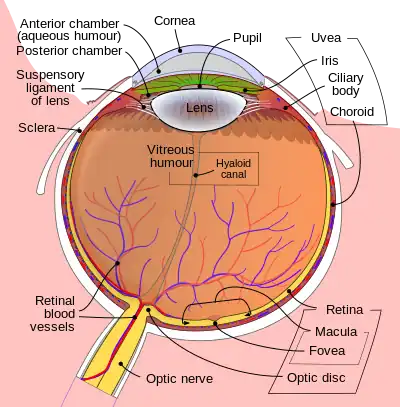

Eye

Light entering the eye is refracted as it passes through the cornea. It then passes through the pupil (controlled by the iris) and is further refracted by the lens. The cornea and lens act together as a compound lens to project an inverted image onto the retina.

Retina

The retina consists of many photoreceptor cells which contain particular protein molecules called opsins. In humans, two types of opsins are involved in conscious vision: rod opsins and cone opsins. (A third type, melanopsin in some retinal ganglion cells (RGC), part of the body clock mechanism, is probably not involved in conscious vision, as these RGC do not project to the lateral geniculate nucleus but to the pretectal olivary nucleus.[25]) An opsin absorbs a photon (a particle of light) and transmits a signal to the cell through a signal transduction pathway, resulting in hyper-polarization of the photoreceptor.

Rods and cones differ in function. Rods are found primarily in the periphery of the retina and are used to see at low levels of light. Each human eye contains 120 million rods. Cones are found primarily in the center (or fovea) of the retina.[26] There are three types of cones that differ in the wavelengths of light they absorb; they are usually called short or blue, middle or green, and long or red. Cones mediate day vision and can distinguish color and other features of the visual world at medium and high light levels. Cones are larger and much less numerous than rods (there are 6-7 million of them in each human eye).[26]

In the retina, the photoreceptors synapse directly onto bipolar cells, which in turn synapse onto ganglion cells of the outermost layer, which then conduct action potentials to the brain. A significant amount of visual processing arises from the patterns of communication between neurons in the retina. About 130 million photo-receptors absorb light, yet roughly 1.2 million axons of ganglion cells transmit information from the retina to the brain. The processing in the retina includes the formation of center-surround receptive fields of bipolar and ganglion cells in the retina, as well as convergence and divergence from photoreceptor to bipolar cell. In addition, other neurons in the retina, particularly horizontal and amacrine cells, transmit information laterally (from a neuron in one layer to an adjacent neuron in the same layer), resulting in more complex receptive fields that can be either indifferent to color and sensitive to motion or sensitive to color and indifferent to motion.[27]